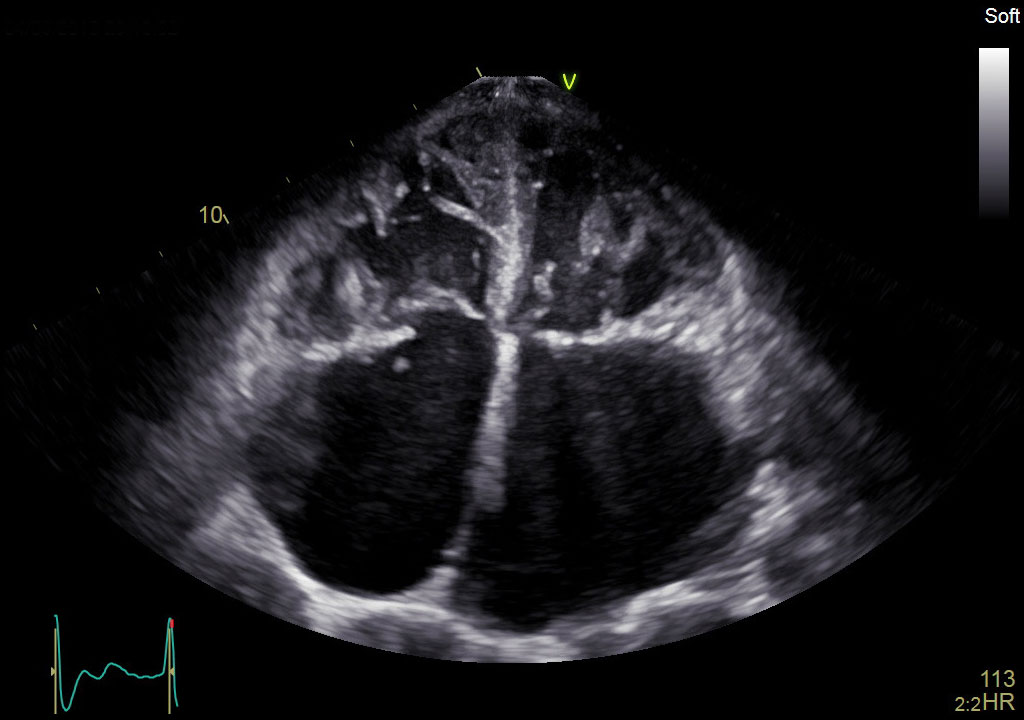

Объединяя проверенную мощность и производительность линейки Vivid с мощной программной платформой формирования ультразвукового луча cSound для реконструкции изображений, система Vivid E90 переносит ультразвуковую диагностику на совершенно новый уровень, помогая минимизировать неинформативные исследования и снизить стоимость услуг.

В сравнении с многими традиционными аппаратами УЗД эта система позволяет получать больше данных, используя технологии точной конфокальной визуализации (TCI) и адаптивного контрастного усиления (ACE) для получения изображений высочайшего качества. Кроме этого система оснащена многими высокоточными инструментами количественного анализа и функциями, оптимизирующими рабочий процесс.

- Детализированное отображение структур сердца для улучшения взаимодействия между врачами УЗД и интервенционными кардиологами (хирургами).

- Улучшенные характеристики:

- качества изображений в ближней зоне обзора;

- четкости отображения латеральных стенок;

- однородности изображений;

- проникновения.